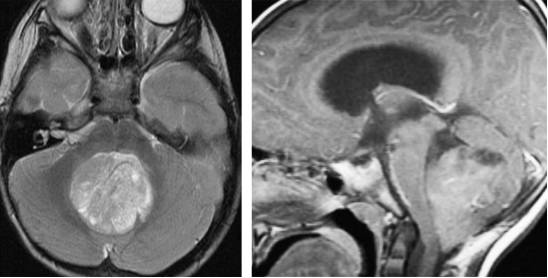

图5. 髓母细胞瘤在T1相上相对白质呈低信号,往往呈不均匀强化。在T2相上,由于钙化、坏死和囊性变的存在往往表现为混杂信号。

图3. 图示为向四脑室延伸和压迫的蚓部毛细胞星形细胞胶质瘤。肿瘤呈囊性,伴有明显强化的结节。囊壁未见强化,无需手术切除。